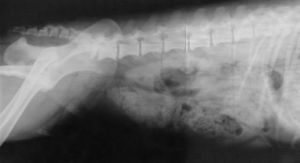

Sie sind hier: Startseite Nachrichten Gesundheit Dänemark: Mehr Infektionen nach Hüftfrakturen Hüfte: OPs erhöhen das Infektionsrisiko stark.

Hüfte: OPs erhöhen das Infektionsrisiko stark.